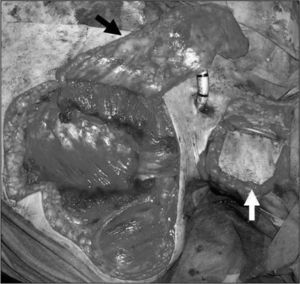

ResultadosObservamos que la extensión de la cirugía a la faringe es el único factor asociado significativamente (p=0,04) a la aparición de fístulas en nuestro medio (odds ratio [OR] = 2,83). La asociación de radioterapia previa y vaciamientos cervicales muestra una tendencia importante (OR = 3,2), no significativa (p=0,099). Otros factores como la edad del paciente, la radioterapia previa, los vaciamientos cervicales, la traqueotomía previa o la hemoglobina postoperatoria no se asocian estadísticamente a la aparición de esta complicación. La mayoría de las fístulas se cierran con medidas conservadoras (72,7 %), pero en pacientes irradiados previamente requieren reparación quirúrgica con mayor frecuencia que en los no irradiados (p <0,01).

ResultsThe only risk factor with statistical significance (P=.04) for the onset of fistulae in our setting is the extension of the surgery to the pharynx (OR=2.83). The association of prior radiotherapy and concurrent neck dissection displayed a notable trend (OR=0.32) but without significance (P=.099). Patient age, prior radiotherapy, concurrent neck dissection, prior tracheotomy and post-operative haemoglobin level did not predispose to this complication in our study. Non-surgical closure of the pharyngocutaneous fistula was achieved in most cases (72.7 %) but patients who had pre-operative radiotherapy required surgical closure more frequently (P<.01) than those not irradiated.